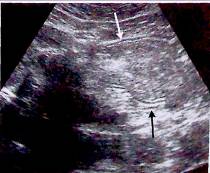

![]()

Рис.29. Поражение терминального отдела подвздошной кишки: гипоэхогенное утолщение стенки (TI) Определяются свищевые ходы (F), проходящие через брюшину и переднюю брюшную стенку (AW); некоторые ходы заканчиваются слепо.